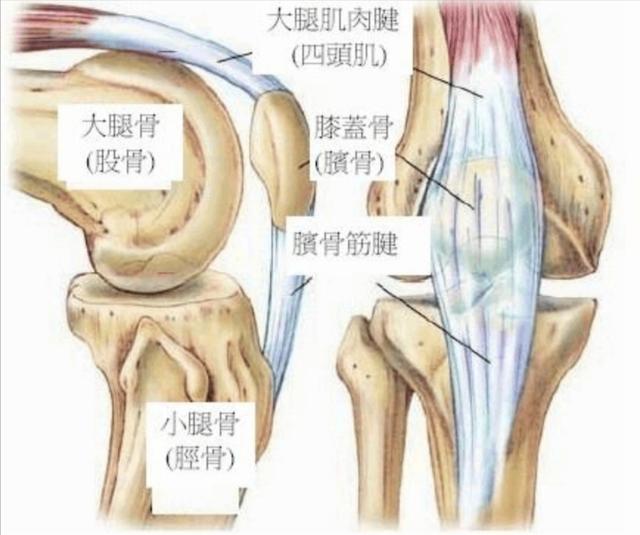

在我们骨科门诊啊,膝关节疼痛,是五大常见症状之一。来骨科门诊看膝关节疼痛的不仅有六七十岁的老年人,四五十岁中年人,还有很多二三十岁的青年人,他们其中有将近一半出现以下的症状,就是膝关节在上下楼梯或者蹲起的时候,有困难、有僵硬、有疼痛感,但是大多数时候平地走路倒没什么感觉。很多人非常不解,这到底是什么原因?其实这在我们膝关节领域,非常常见,看懂了这幅解剖图,您就知道原因了。

我们的膝关节实际上有三块骨头组成,分别是大腿骨,小腿骨,还有膝盖正面的、圆形的髌骨。髌骨是我们每个人都能摸到的,你用手放在你的膝盖正前方就能触摸到一个圆形的,像盖子一样的圆骨头,只要你的大腿肌肉是放松状态,那么髌骨就是可以左右推动的。那么既然是三块骨头,它们就构成了两个不同的接触面。一个呢,很好理解,是大腿和小腿骨之间的接触面,这个关节面是让我们负重用的。不论我们是站着、走路、跳跃,只要有体重压在膝盖上,这个关节面就承担压力。而我们人体膝关节的结构,决定了内侧关节受力多,约占整个重量的60?外侧关节面受力少,约占40?所以往往都是膝盖内侧磨损的快,内侧关节间隙,首先出现狭窄,所以很多人膝关节炎,刚开始的症状会有膝盖内侧的疼痛,久而久之,也会出现O型腿,也叫膝内翻,这就是因为膝盖内侧的软骨等结构已经被磨损殆尽。